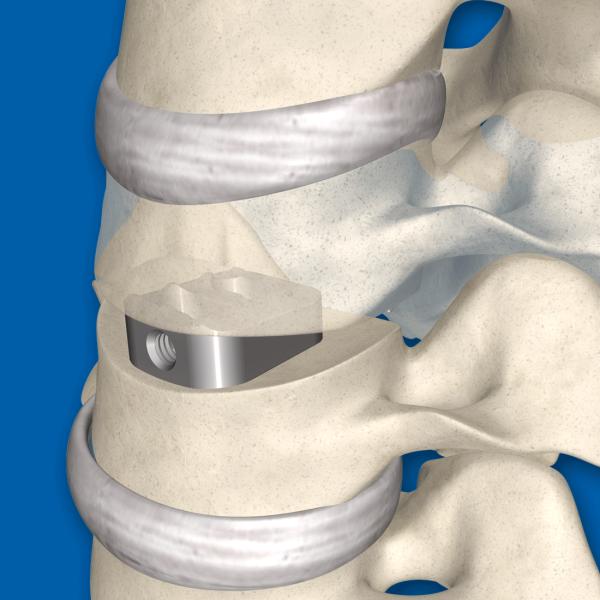

| Categories | Cornerstone Peek Cage |

Orthopedic PEEK Cervical Cage, Lumbar Cage Interbody Fusion Device,Spinal Fixation System,Peek Cervical Lumbar Cage

1. Perforated structure for bone ingrowth and throughgrowth

2. Roughened surface promotes integration and bone ongrowth

Interbody fusion places the bone graft between the vertebra in the area usually occupied by the intervertebral disc. In preparation for the spinal fusion, the disc is removed entirely, for example in ACDF. A device may be placed between the vertebra to maintain spine alignment and disc height. The intervertebral device may be made from either plastic or titanium. The fusion then occurs between the endplates of the vertebrae. Using both types of fusion is known as 360-degree fusion. Fusion rates are higher with interbody fusion. Three types of interbody fusion are:

1. Anterior lumbar interbody fusion (ALIF)- the disc is accessed from an anterior abdominal incision

2. Posterior lumbar interbody fusion (PLIF) - the disc is accessed from a posterior incision

3. Transforaminal lumbar interbody fusion (TLIF) - the disc is accessed from a posterior incision on one side of the spine

For internal fixation of spinal fractures

Indications

| 1 | Narrow lumbar spinal canal |

| 2 | Pseudarthrosis or failed arthrodesis |

| 3 | Degenerative disc disease and spinal instability |

| 4 | Degenerative spondylolisthesis |

| 5 | Spondylolisthesis with stenosis |